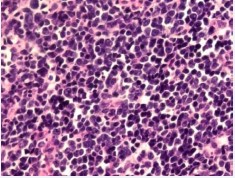

The result of pathology of the mass indicated lymphocytic infiltration and necrotic change (Figure 3).

Figure 3: Specimen revealed lymphocytic infiltration and necrotic change.(HE×400).